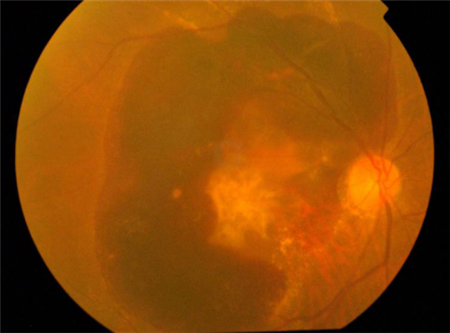

而湿性黄斑变性,其成因是脉络膜出现了非正常的新生血管,这些新生血管很容易发生渗漏和出血。若未及时治疗,渗出物及血液会聚集与黄斑区,并破坏区域内的感光细胞,对视力造成极大威胁。

与恶化缓慢的干性黄斑病变不同,湿性黄斑病变恶化速度非常快,症状也较为明显,表现为视物变形、中心视力下降、视野中心有暗点等症状。若出现这些症状,需立即就医,否则可能造成不可弥补的视力受损。